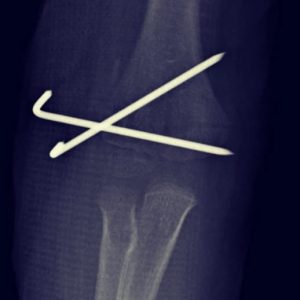

- Fracturas de codo

- Fractura supracondílea

Fractura supracondílea de humero